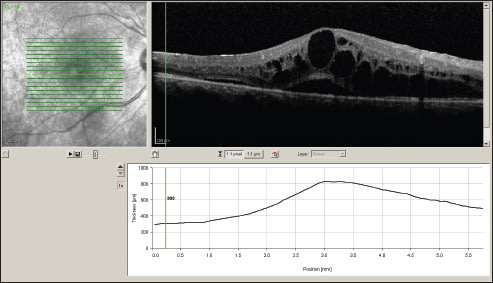

After the risks and benefits of systemic immunomodulatory and local therapy were explained, the patient elected to have Retisert placement in her left eye. Visual acuity improved to 20/80 four weeks after treatment. Eight weeks after treatment, acuity was 20/60.

Two months after implant placement OS, the right eye was implanted. VA was 20/200 OD and 20/60 OS at that time. Four weeks after implantation OD, VA improved to 20/60 OD, and then to 20/40 OD eight weeks later (Figure 3). OCT nine months later showed dramatic resolution of CME (Figure 4). The pre-existing PSC cataract progressed. Phacoemulsification surgery with in-the-bag IOL implantation was performed OS 11 months after Retisert implantation in that eye. Vision improved from 20/80 to 20/50 after the surgery.

Figure 3. OCT of the left eye (upper image) and right eye (lower image) after Retisert placement.